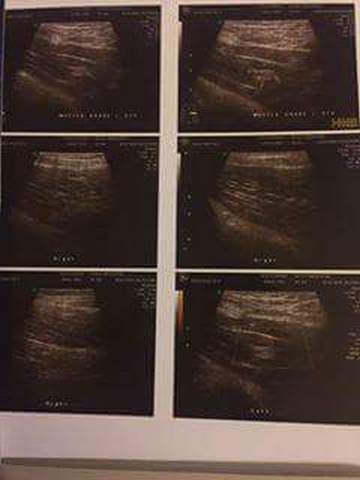

وقام حارس الأبيض، بنشر كافة الشهادات الطبية والاشعة التي قام بها في الفترة الماضية، والتي تؤكد عدم قدرته على خوض المران.